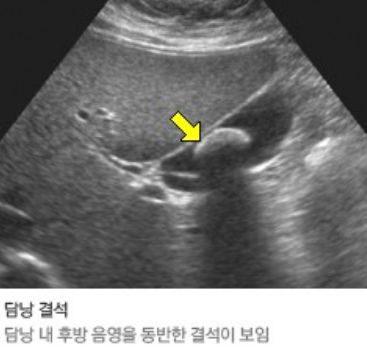

간의 실질 크기와 간내 혈관의 크기, 간의 미만성 또는 국소적 병소, 담낭 및 담관의 구조 및 확장 여부를 알 수 있고,